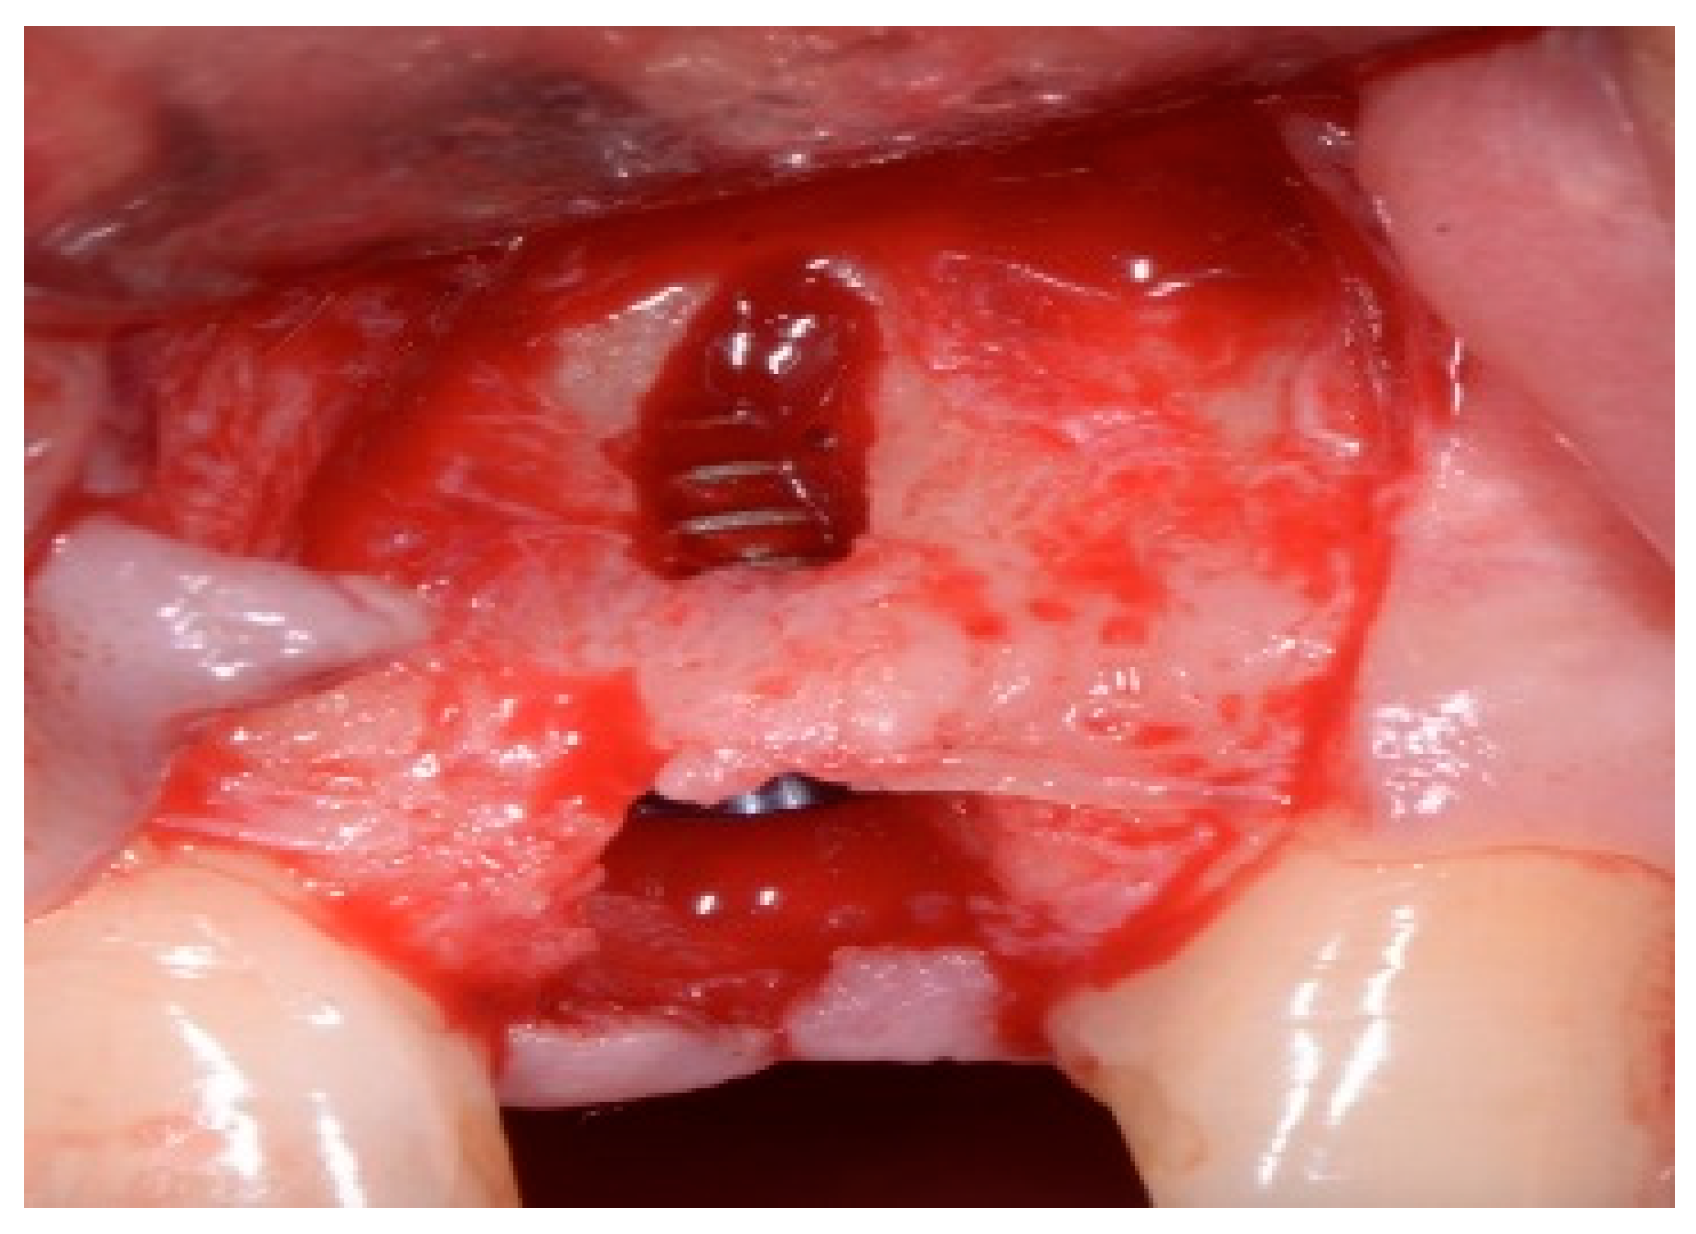

One hour before the surgical procedure, the patient received a prophylactic dose of 1 g of amoxicillin. Following local anesthesia, surgical access was obtained by raising a full-thickness aesthetic flap extending to the distal line angles of the lateral incisors. The full-thickness flap was extended 3–5 mm beyond the apical margin of the defect. The two central incisor roots were extracted, and the sockets were curetted with surgical curettes to remove all the granulation tissue (Figure 2). The sockets were assessed for the presence of a dehiscence and or fenestration. Two implants (Adin Dental Implants, Englewood, NJ, 07632, USA) were placed according to the manufacturer’s instructions (Figure 3).

Figure 2.

Clinical view immediately after extraction.

Figure 3.

Clinical view of the placement of two maxillary anterior implants.